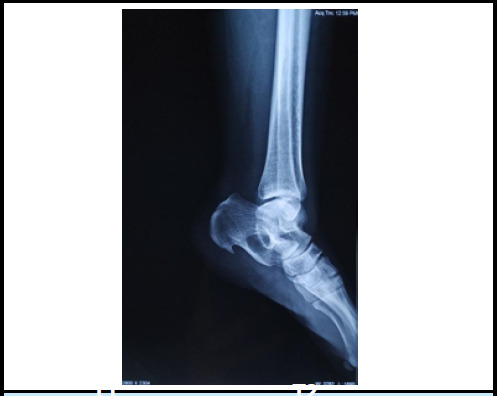

摘要:骨内脂肪瘤是导致足跟疼痛的罕见原因。钙骨是骨内脂肪瘤的典型受累部位。关于小跟骨内脂肪瘤的发表文章寥寥无几,其中一篇来自尼泊尔。我们报告了一例 35 岁女性病例,患者左足跟痛 1 年。疼痛逐渐加剧,严重到无法进行日常生活活动。她接受了刮除手术,并用骨水泥填充了缺损处。在 2.5 年的随访中,没有发现残余疼痛。我们简要回顾了骨内脂肪瘤的假设发病机制、临床表现、诊断和各种治疗方法。骨科医生应高度怀疑足跟痛的罕见病因及其可能的治疗方法。当保守方法不能缓解症状时,手术切除并用骨水泥填充缺损处可长期缓解症状。

Abstract: Intraosseous lipoma of calcaneum is a rare cause of heel pain. Calcaneum is a typical site of involvement of IOL. There are only a few published articles regarding calcaneal intraosseous lipoma and one has been reported from Nepal. We report a case of 35 years female who presented with left heel pain for 1 year. The pain was gradually increasing in intensity and was severe enough to refrain her from activities of daily living. She was surgically operated with curettage and filling the defect with bone cement. There is no residual pain at 2.5 years follow up. We briefly review the postulated pathogenesis, clinical manifestations, diagnosis and various modalities of treatment of intraosseous lipoma. An orthopedic surgeon should have high degree of suspicion regarding the uncommon cause of heel pain and its possible management. When conservative methods do not relieve symptoms, surgical excision and filling the defect with bone cement provides long term relief.